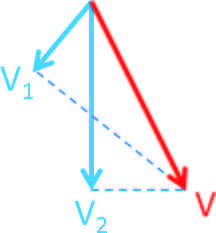

Для того чтобы получить направленный вектор скорости кровотока в любой его точке используются множество разнонаправленных циклов приема-передачи эхосигнала (Рисунок 2). Затем скорость (величина вектора скорости) рассчитывается с помощью метода, изображенного на рисунке 3. Благодаря множественному разнонаправленному сканированию, в каждой исследуемой точке кровотока ультразвуковая система получает вектора скорости в плоскости каждой итерации цикла приема-передачи эхосигнала. Истинный вектор скорости вычисляется путем компаундинга и регрессионного анализа полученных данных. Кроме того, поскольку платформа ZST+ хранит дамп оригинального эхосигнала, то он же используется для формирования изображения в B-режиме, что делает возможным как высокочувствительную регистрацию потока, так и высокое разрешение серошкального изображения.